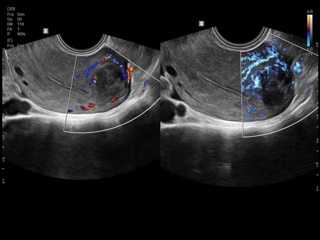

In the section "Оbsterics" of atlas the results of ultrasonic examinations of pregnant women with different durations of gestation are represented. Here you can see images of internally organs, cerebrum, cordis and the sex of the fetus, the sonograms of multiple pregnancy, the blood flow in placenta and umbilical cord, defects of fetal`s development, etc.